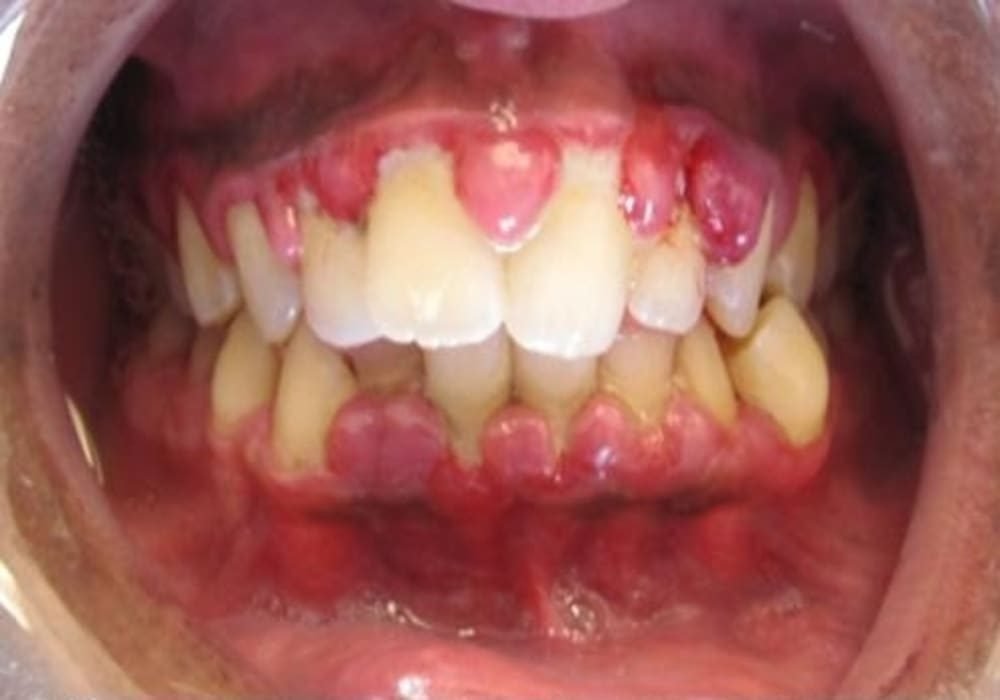

Kasus gusi bengkak (gingivitis) yang parah. Sumber foto: Wikimedia Commons

Gusi bengkak (gingivitis) adalah peradangan pada gusi (jaringan gingiva) yang biasanya terjadi karena penumpukan plak di sekitar garis gusi. Kondisi ini sering membuat gusi merah, nyeri ringan, mudah berdarah saat menyikat gigi atau flossing.

- Gusi merah dan bengkak di sekitar gigi